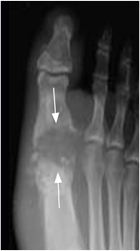

Fig 64 A. Artritis séptica.

Rx AP. Disminución del 4º espacio metacarpofalángico y pérdida en la nitidez de los contornos en la cabeza del metacarpiano, por artritis séptica.

Fig 64 B . Artritis séptica.

Rx AP. Artritis infecciosa del pulgar, con zonas de osteolisis en la base de la falange y la cabeza del metatarsiano. (Flechas). Hay edema asociado de los tejidos blandos.